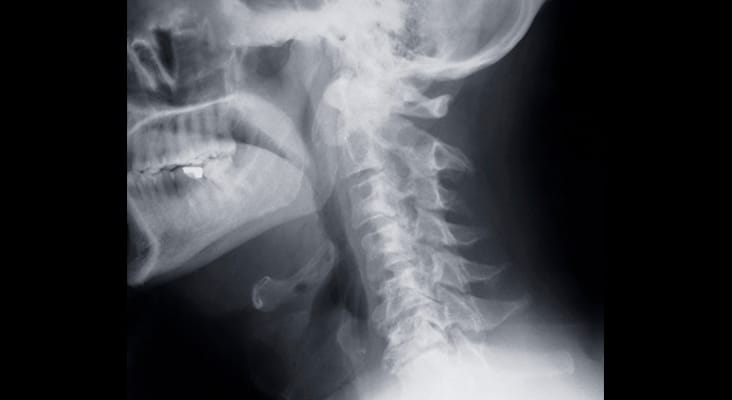

Antiresorptive therapies for individuals with osteoporosis include five principal classes of agents: bisphosphonates, estrogens, selective estrogen receptor modulators, calcitonin, and monoclonal antibodies, such as denosumab. While each has the potential to cause osteonecrosis, bisphosphonates are the most commonly prescribed antiresorptive agents. As such, clinicians should be mindful of strategies that can help these patients maintain optimum oral health.

Photo Credit: ollaweila / iStock / Getty Images Plus